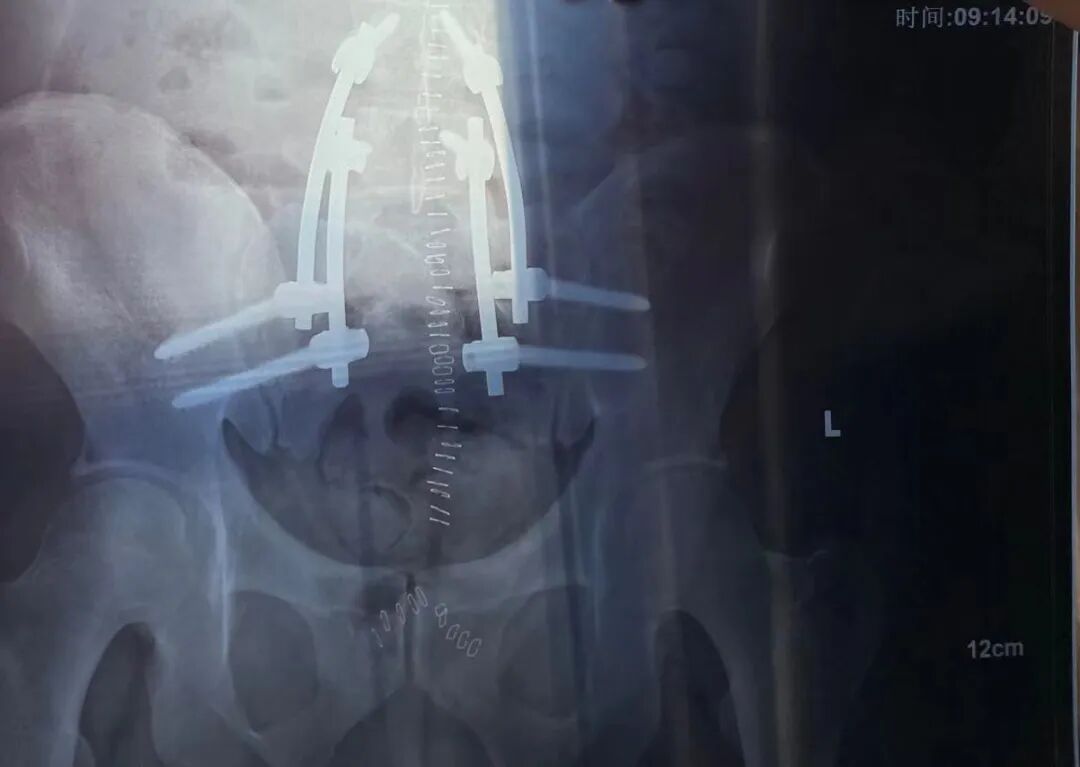

然而事实上,我坐不起来也拆不了管子,我和金刚狼唯一的共同点是我身体里也有一堆钛合金支架,但它们可千万别从我身体里伸出来。

我的钛合金支架丨作者供图